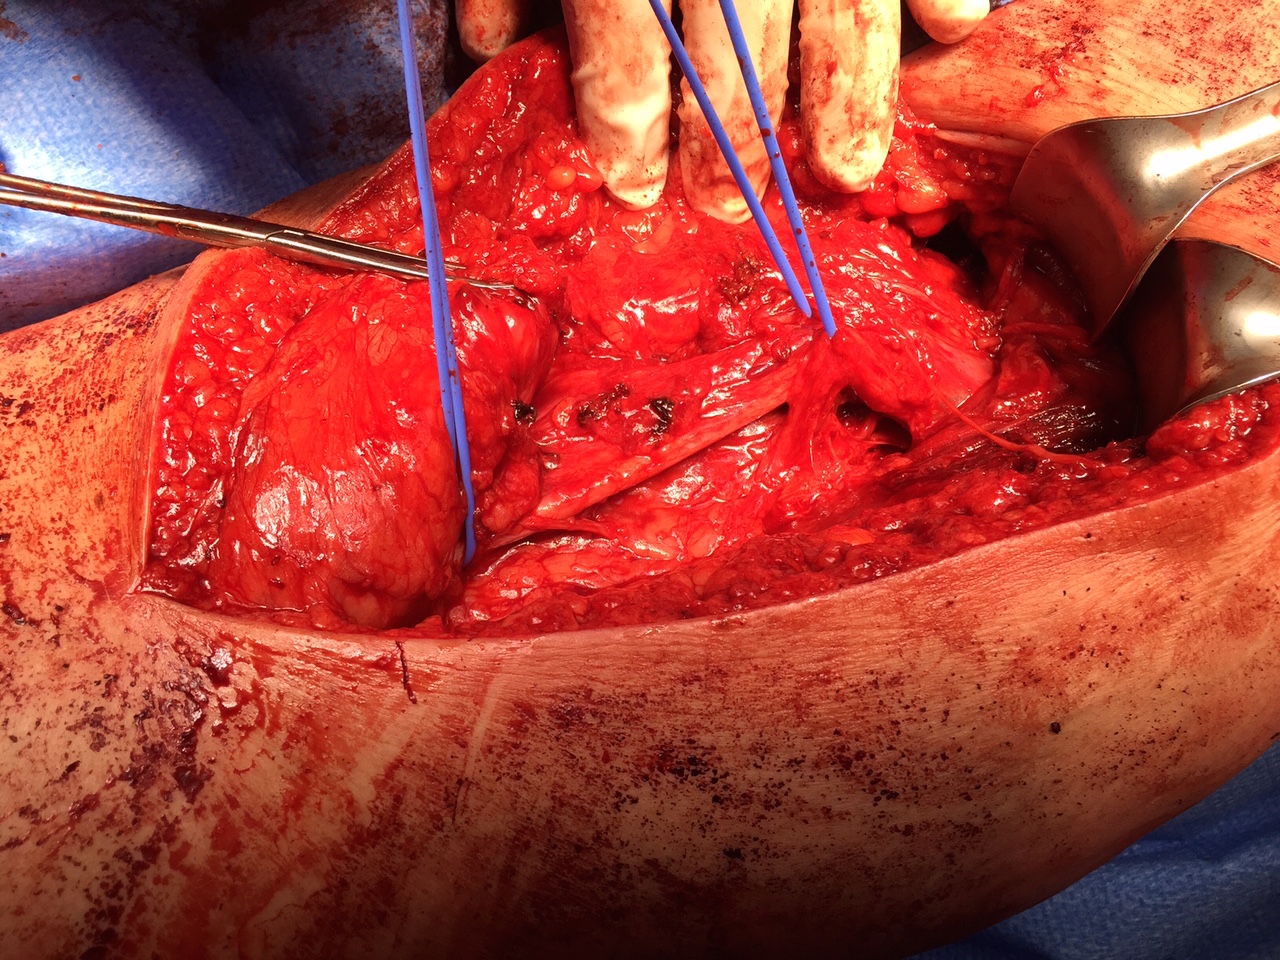

- identify and preserve sciatic nerve (lateral to hamstring)

Hamstring (*) with sciatic nerve lateral to hamstring (blue vessiloop)

Sciatic nerve with blue vessiloops